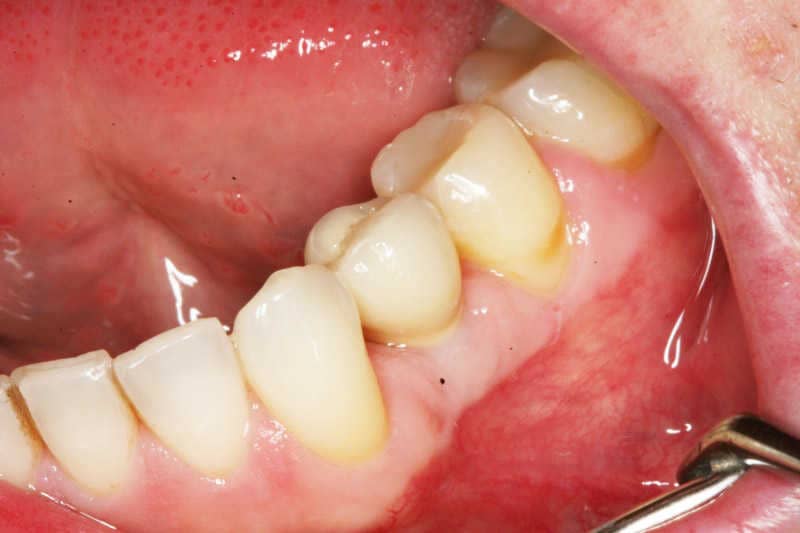

Az implantátumban csavarral rögzülő titán protetikai fejre cementtel rögzülő fémkerámia koronát rögzítettünk.

4

A fémkerámia koronát rögzítettük